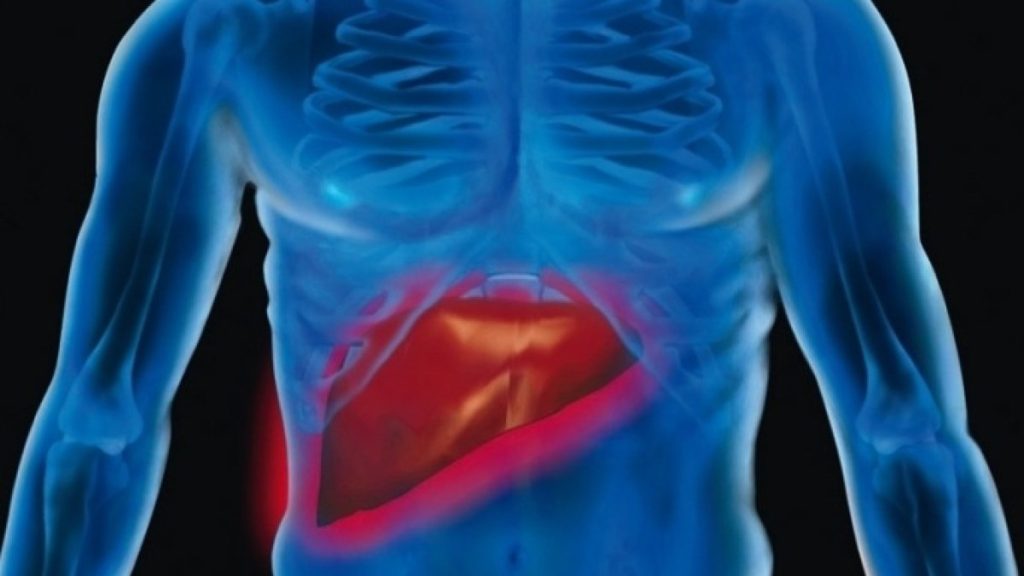

كشفت دراسة حديثة عن إمكانية إطالة عمر المصابين بـسرطان الكبد في المراحل المتقدمة من خلال الجمع بين العلاج المناعي والجراحة، بما في ذلك زراعة الكبد أو استئصال الورم. أظهرت النتائج أن هذا النهج المتكامل يمكن أن يحسن بشكل كبير فرص البقاء على قيد الحياة للمرضى الذين يعانون من هذا المرض الخطير. الدراسة، التي أجراها علماء من مركز سيدارز سيناي للأورام في الولايات المتحدة، تعيد النظر في مسارات العلاج التقليدية وتقدم أملاً جديداً للمرضى.

تحليل بيانات شمل أكثر من 4300 مريض مصاب بـسرطان الكبد كشف عن ارتباط قوي بين الاستجابة للعلاج المناعي وإمكانية الخضوع لعملية جراحية ناجحة. وفقًا للباحثين، فإن العلاج المناعي، على الرغم من أنه لا يعالج السرطان بشكل كامل، يمكن أن يقلص حجم الأورام بما يكفي لجعل الجراحة خيارًا قابلاً للتطبيق. هذه النتائج لها آثار كبيرة على كيفية التعامل مع المرض في المراحل المتأخرة.

أظهرت الدراسة أن معدل الخطر الإجمالي للوفاة ينخفض بنسبة 85٪ للمرضى الذين خضعوا لعملية زراعة الكبد أو استئصال الورم جراحياً بعد تلقي العلاج المناعي، مقارنةً بالمرضى الذين تلقوا العلاج المناعي بمفرده. ويشير هذا إلى أن الجراحة، في أعقاب العلاج المناعي، يمكن أن توفر فرصة علاجية حاسمة. يُعزى هذا التحسن الملحوظ إلى إمكانية التخلص من الأمراض المصاحبة للكبد من خلال زراعة الكبد.

تتضمن الأعراض الشائعة لـسرطان الكبد المتقدم فقدان الوزن غير المبرر، وفقدان الشهية، والشعور بالإرهاق الشديد، واليرقان، وتورم البطن بسبب تراكم السوائل. يتم عادةً علاج هذه المرحلة من المرض من خلال مجموعة متنوعة من الخيارات، بما في ذلك الأدوية الموجهة، والعلاج المناعي، والعلاج الكيميائي الموضعي، مع التركيز بشكل كبير على تحسين نوعية حياة المريض. العلاج الموجه يعتمد على استهداف الجزيئات المحددة التي تغذي نمو الورم.